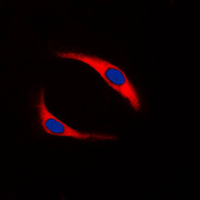

Immunofluorescent analysis of SYK (Phospho-Y323) staining in Ramos cells. Formalin-fixed cells were permeabilized with 0.1% Triton X-100 in TBS for 5-10 minutes and blocked with 3% BSA-PBS for 30 minutes at room temperature. Cells were probed with the primary antibody in 3% BSA-PBS and incubated overnight at 4 °C in a humidified chamber. Cells were washed with PBST and incubated with a DyLight 594-conjugated secondary antibody (red) in PBS at room temperature in the dark. DAPI was used to stain the cell nuclei (blue).